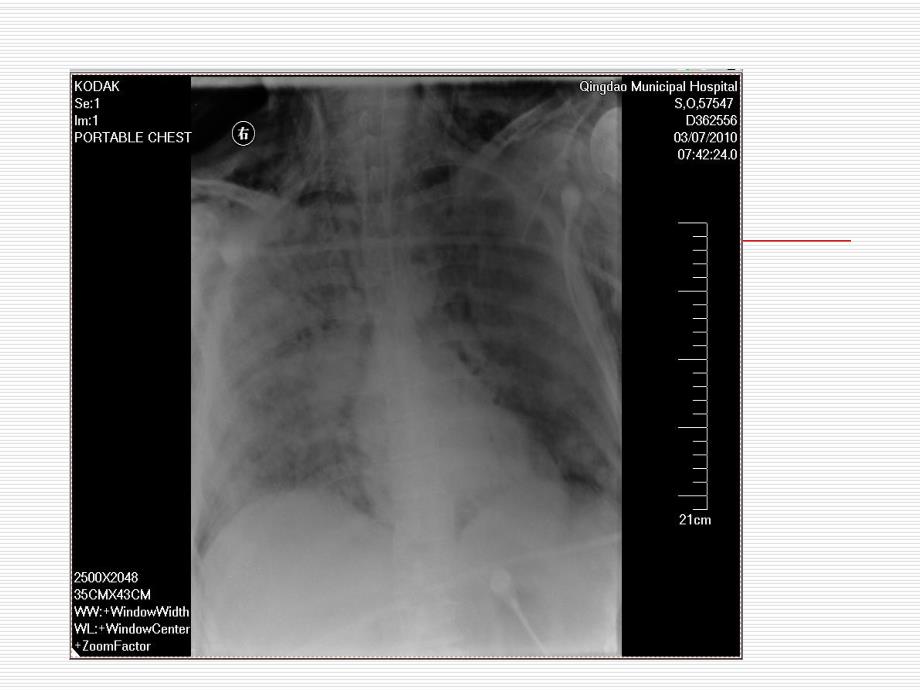

10、阻力Increased RawHigher PTA顺应性降低的原因顺应性降低的原因o 肺僵硬肺僵硬 水肿水肿 实变实变 纤维化纤维化 肺不张肺不张o 胸壁僵硬胸壁僵硬 脊柱侧弯或其他胸壁畸形脊柱侧弯或其他胸壁畸形 肥胖肥胖 腹水或腹胀腹水或腹胀o 肺受压肺受压 气胸气胸 胸腔积液胸腔积液o 动态肺充气动态肺充气反映肺顺应性反映肺顺应性-高压报警高压报警Lung Compliance Changes and the P-V LoopPreset PIPVT levelsCOMPLIANCEIncreasedNormalDecreasedPressure Targeted Ventilation压